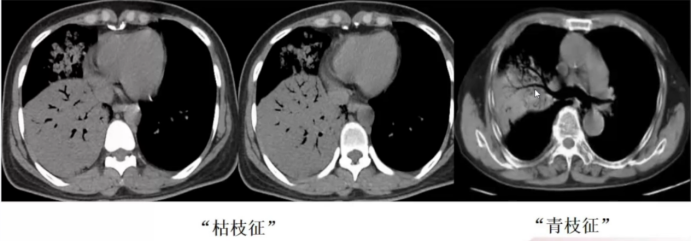

入院后胸片及胸部CT显示:右上肺、右中肺及左下肺可见磨玻璃影;右下肺存在大片实变影,但肺容积基本正常,仅轻度缩小,提示病变可能为慢性或亚急性过程(急性重症感染常伴随肺容积明显缩小);病灶内可见支气管充气征,支气管形态异常——未呈现正常的“由粗变细”趋势,反而局部扩张、僵直,形成“枯枝征”;此外还可见“青枝征”(支气管形态正常,结构清晰)(图2)

图片

2  “枯枝征”和“青枝征”表现

“枯枝征”形成的主要机制是牵拉作用,常见于机化、肿瘤等情况。具体而言,当存在支气管周围结构发生病变时,如伴行的动脉、淋巴及间质,或支气管周围的肺泡发生病变时,尤其当这些病灶发生机化或出现肿瘤时,会对支气管形成牵拉作用导致其扩张,形成“枯枝征”。